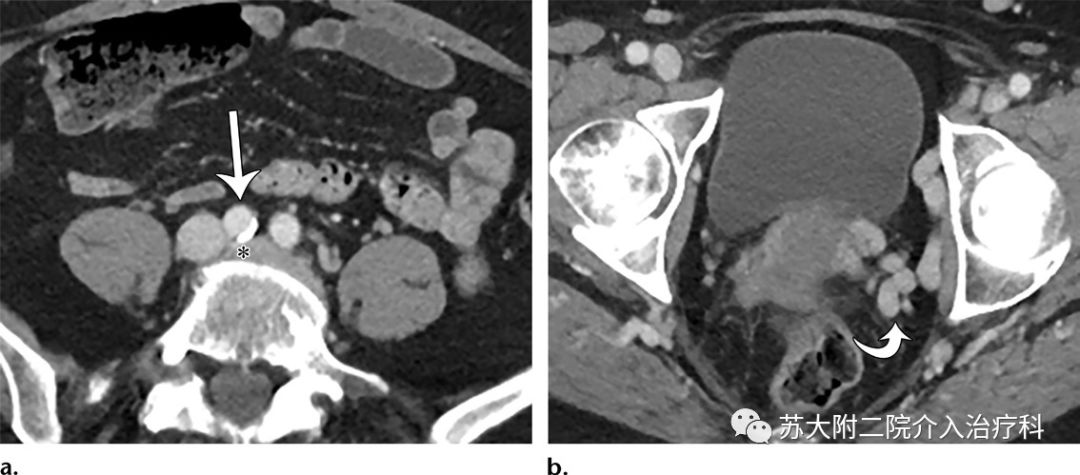

微创介入是一种先进的医疗技术,通过导管将药物直接送达盆腔淤血部位,药物作用直接,效果显著,微创介入还可以配合其他治疗方法,如激光治疗、射频消融等,达到更好的治疗效果。